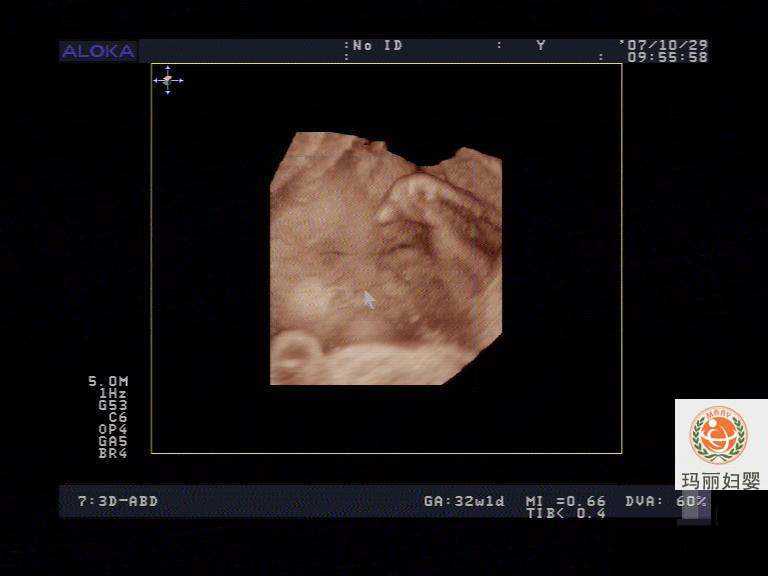

超声描述:

宫内胎儿头位,双顶径9.0CM,头围32.0CM,腹围28.0CM,股骨长5.2CM,肱骨长4.4CM,胎心率122次/

分,超声孕周/孕周:33.0/32.1,HC/AC:1.14。

胎儿颅内第三脑室后方脑中线可见一囊性无回声1.4×1.4CM,似与三脑室相通;

胎儿上唇回声连续中断,宽1.4CM。

胎儿腹部脐带起始部膨大范围2.5×2.7CM,内见肠管样偏强回声团;

胎儿双肾回声偏强,左肾大小3.2×2.4×2.2CM,右肾大小3.7×2.5×1.9CM;

胎盘位于子宫后壁成熟度I级,羊水指数16.5CM,羊水最大深度5.0CM,脐动脉S/D:2.26;

超声提示:

单活胎,头位

胎儿复合畸形

1、胎儿颅内囊性无回声,待查

2、胎儿唇裂

3、胎儿脐膨出

4、胎儿肾脏发育异常,胎儿婴儿型多囊肾?

5、胎儿四肢短小,软骨发育不全?